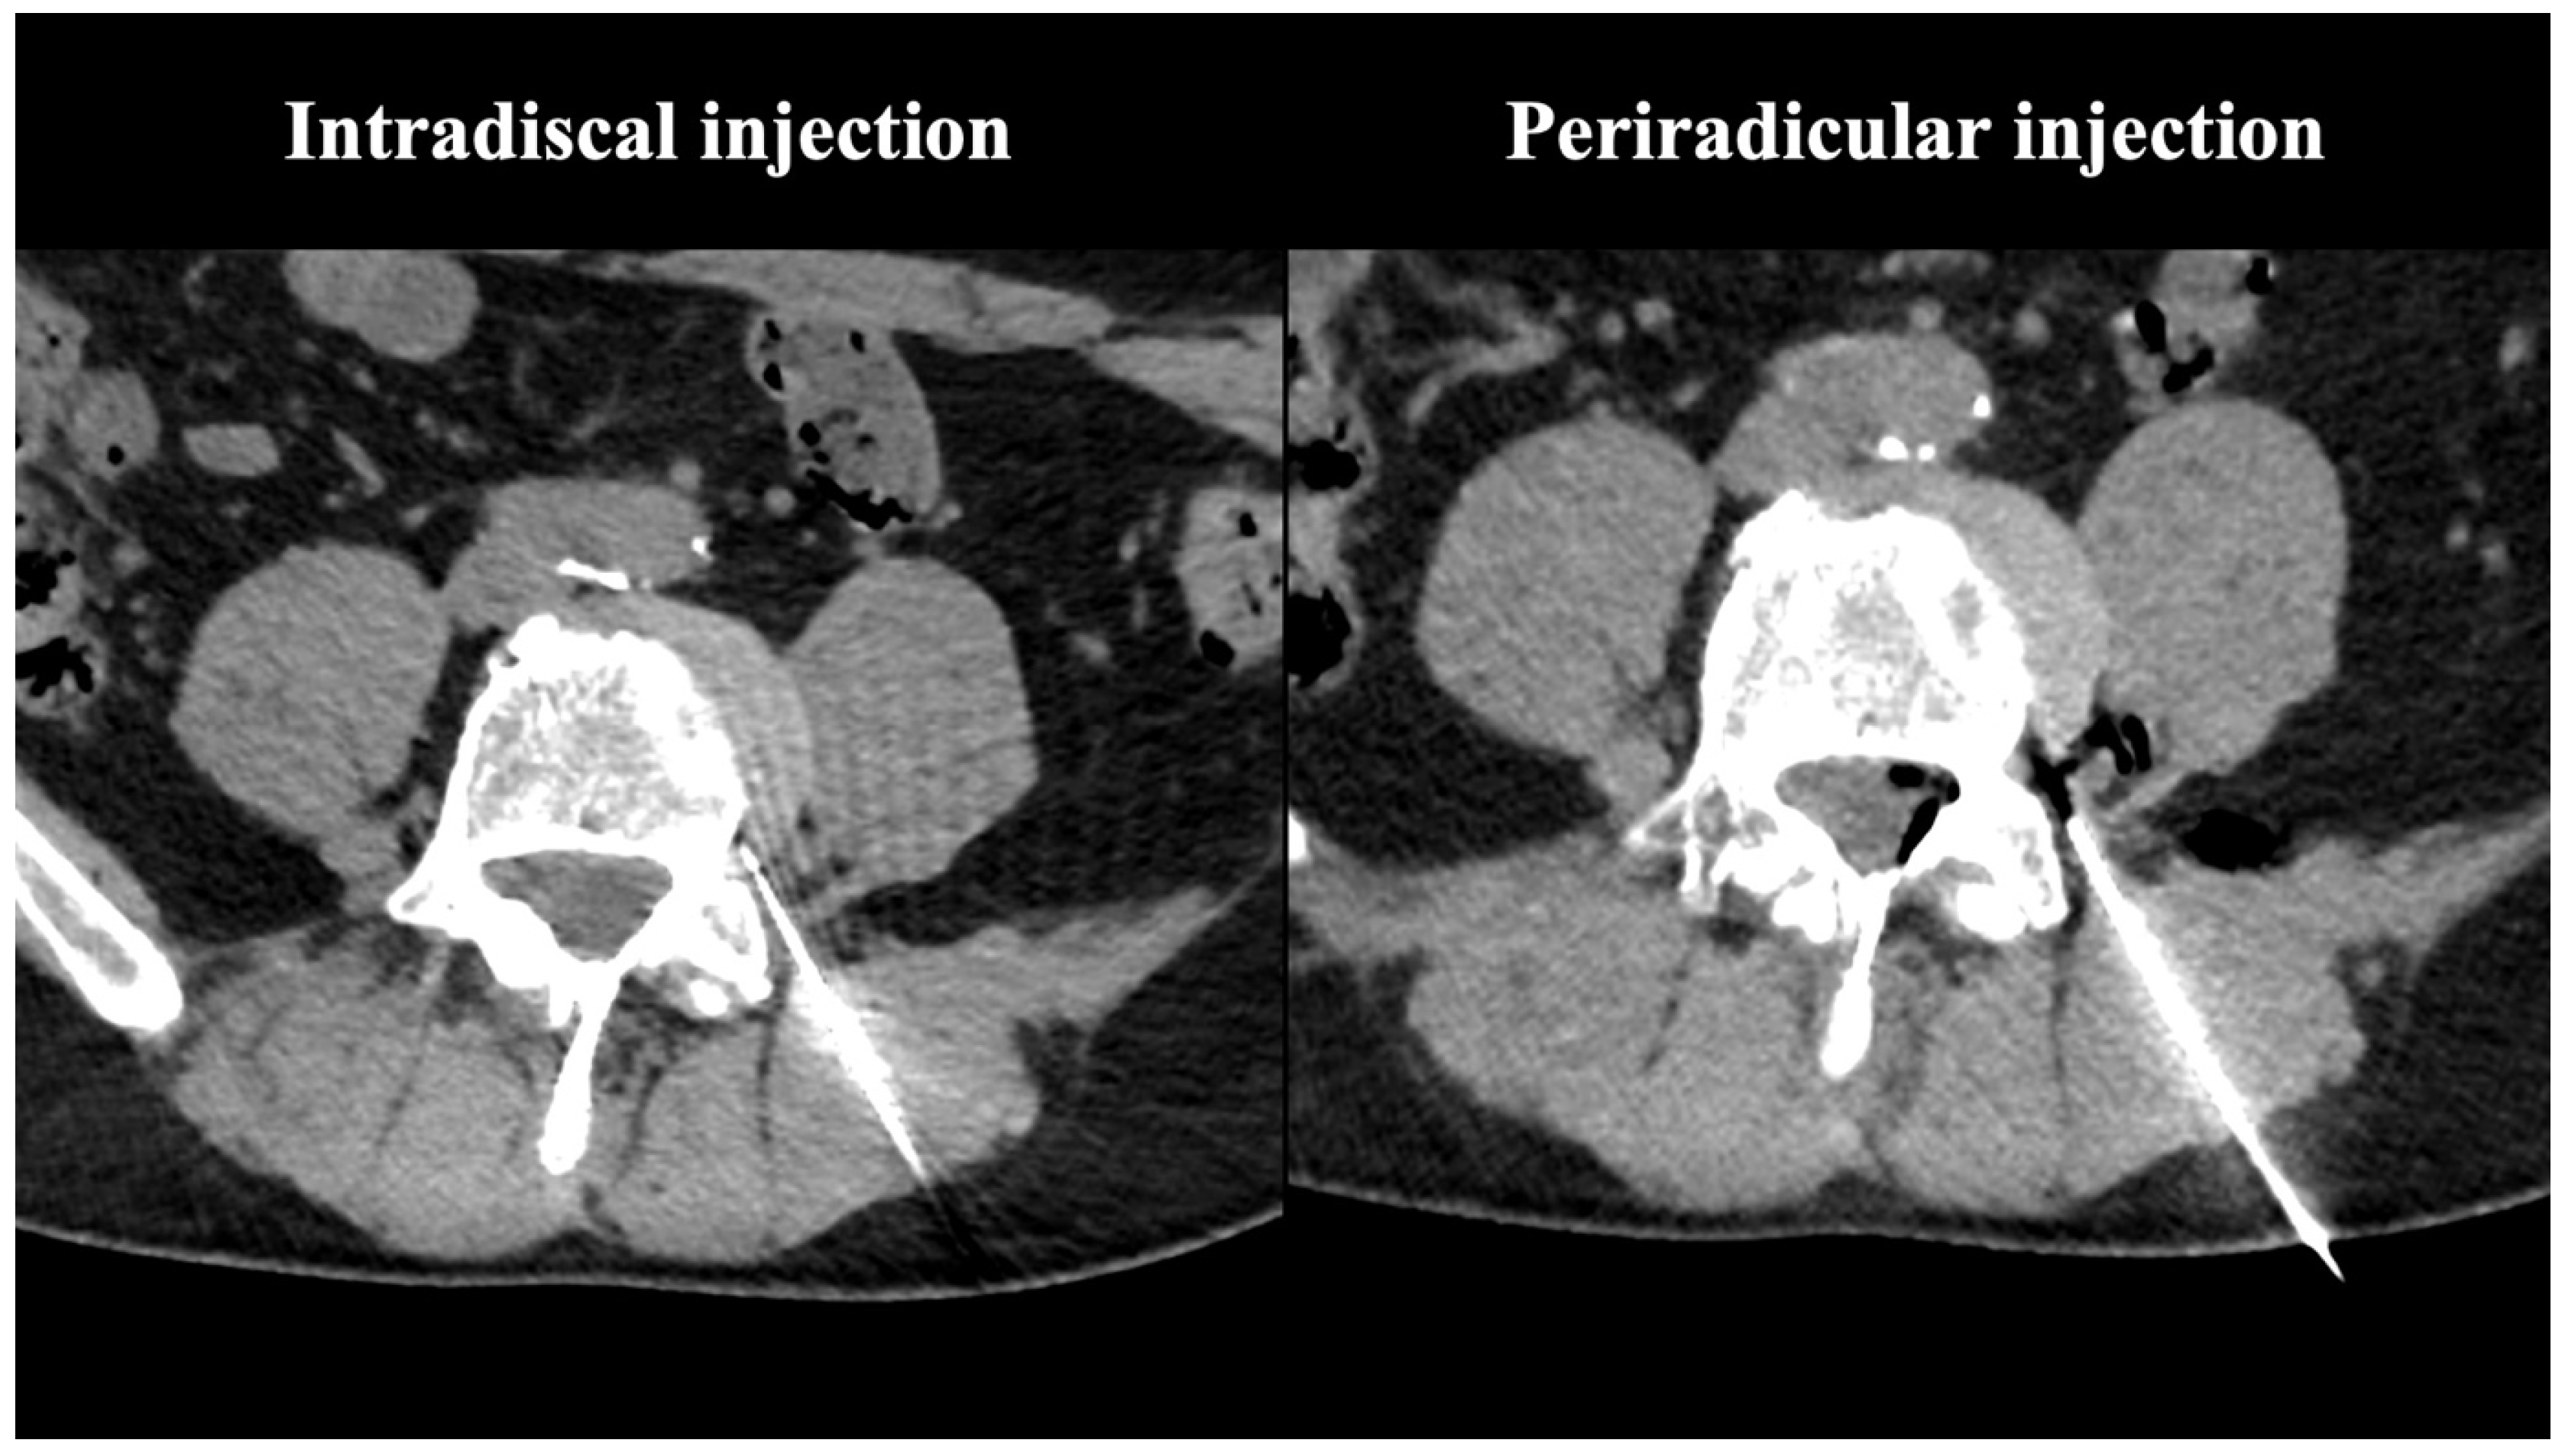

3.1. Procedural Technical Outcome

- Muto, M.; Andreula, C.; Leonardi, M. Treatment of herniated lumbar disc by intradiscal and intraforaminal oxygen-ozone (O2-O3) injection. J. Neuroradiol. 2004, 31, 183–189. [Google Scholar] [CrossRef] [PubMed]

- Giurazza, F.; Guarnieri, G.; Murphy, K.J.; Muto, M. Intradiscal O2O3: Rationale, Injection Technique, Short- and Long-term Outcomes for the Treatment of Low Back Pain Due to Disc Herniation. Can. Assoc. Radiol. J. 2017, 68, 171–177. [Google Scholar] [CrossRef]